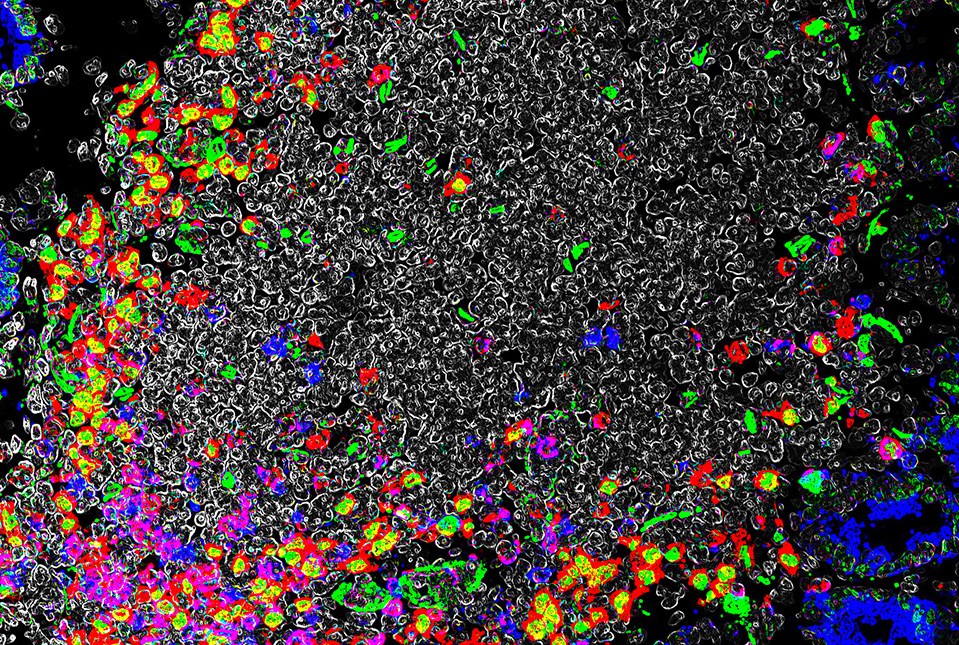

The gut relies heavily on local immune cells with distinct properties, complicating efforts to understand gut immunology. For example, prior research has shown that immune tolerance in the gut is enforced largely by a distinct subset of regulatory T cells called Treg cells that express the transcription factor RORγt. The Sonnenberg lab has been at the forefront of this area of research, where they were the first to discover novel antigen-presenting cells (APCs) expressing RORγt that are enriched in the gut and necessary for immune tolerance. Drs. Lyu and Sonnenberg and their colleagues also have found that gut RORγt+ Treg cells are dependent upon direct signals from these RORγt+ APCs.

To the scientists’ surprise, the usual “Signal Two” coupling of Treg cells and APC receptors, in the presence of Signal One, did not trigger an expansion of gut RORγt+ Treg cells. What did work was—in combination with Signal One—blocking that Signal Two coupling, which expanded the gut RORγt+ Treg cells and prevented gut inflammation in a preclinical model. Importantly, this is the exact opposite to what happens with conventional Treg cells outside of the gut, further highlighting the unique and complicated features of the intestinal immune system.